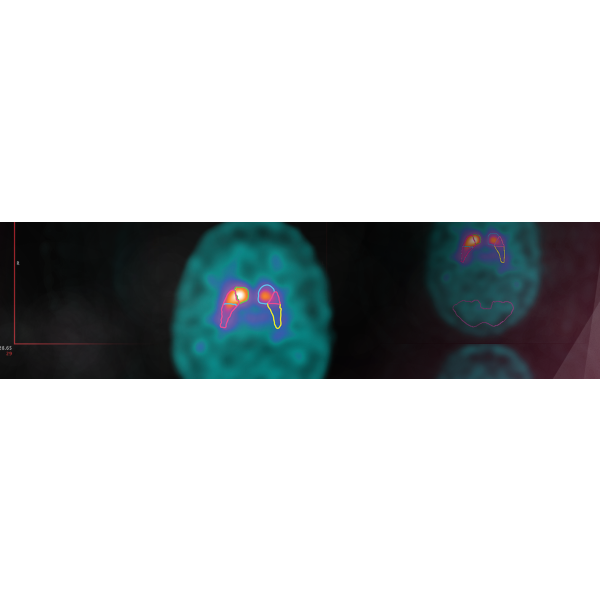

Easy Visual Analysis

Voxel-based analysis with color-coded overlays.

Cluster analysis to refine your results for more confident interpretation.

Region-based analysis with Z-score tables and SUVR statistics.

Cortical surface projections for an overall visual perception.